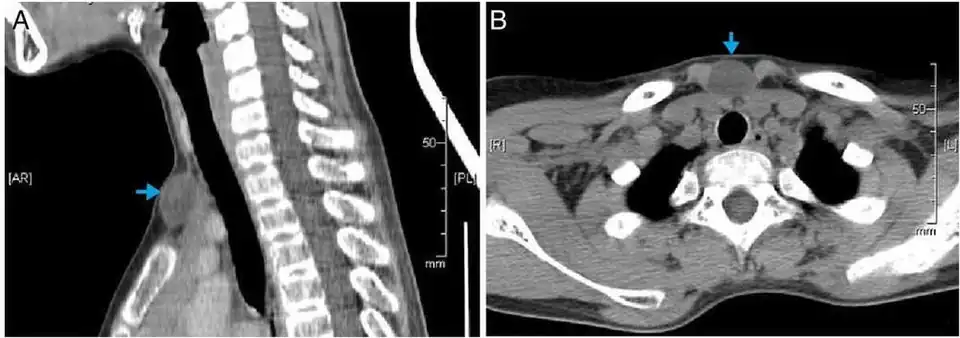

CT scan, showing a homogenous hypodense volume (unspecific cyst-like) -